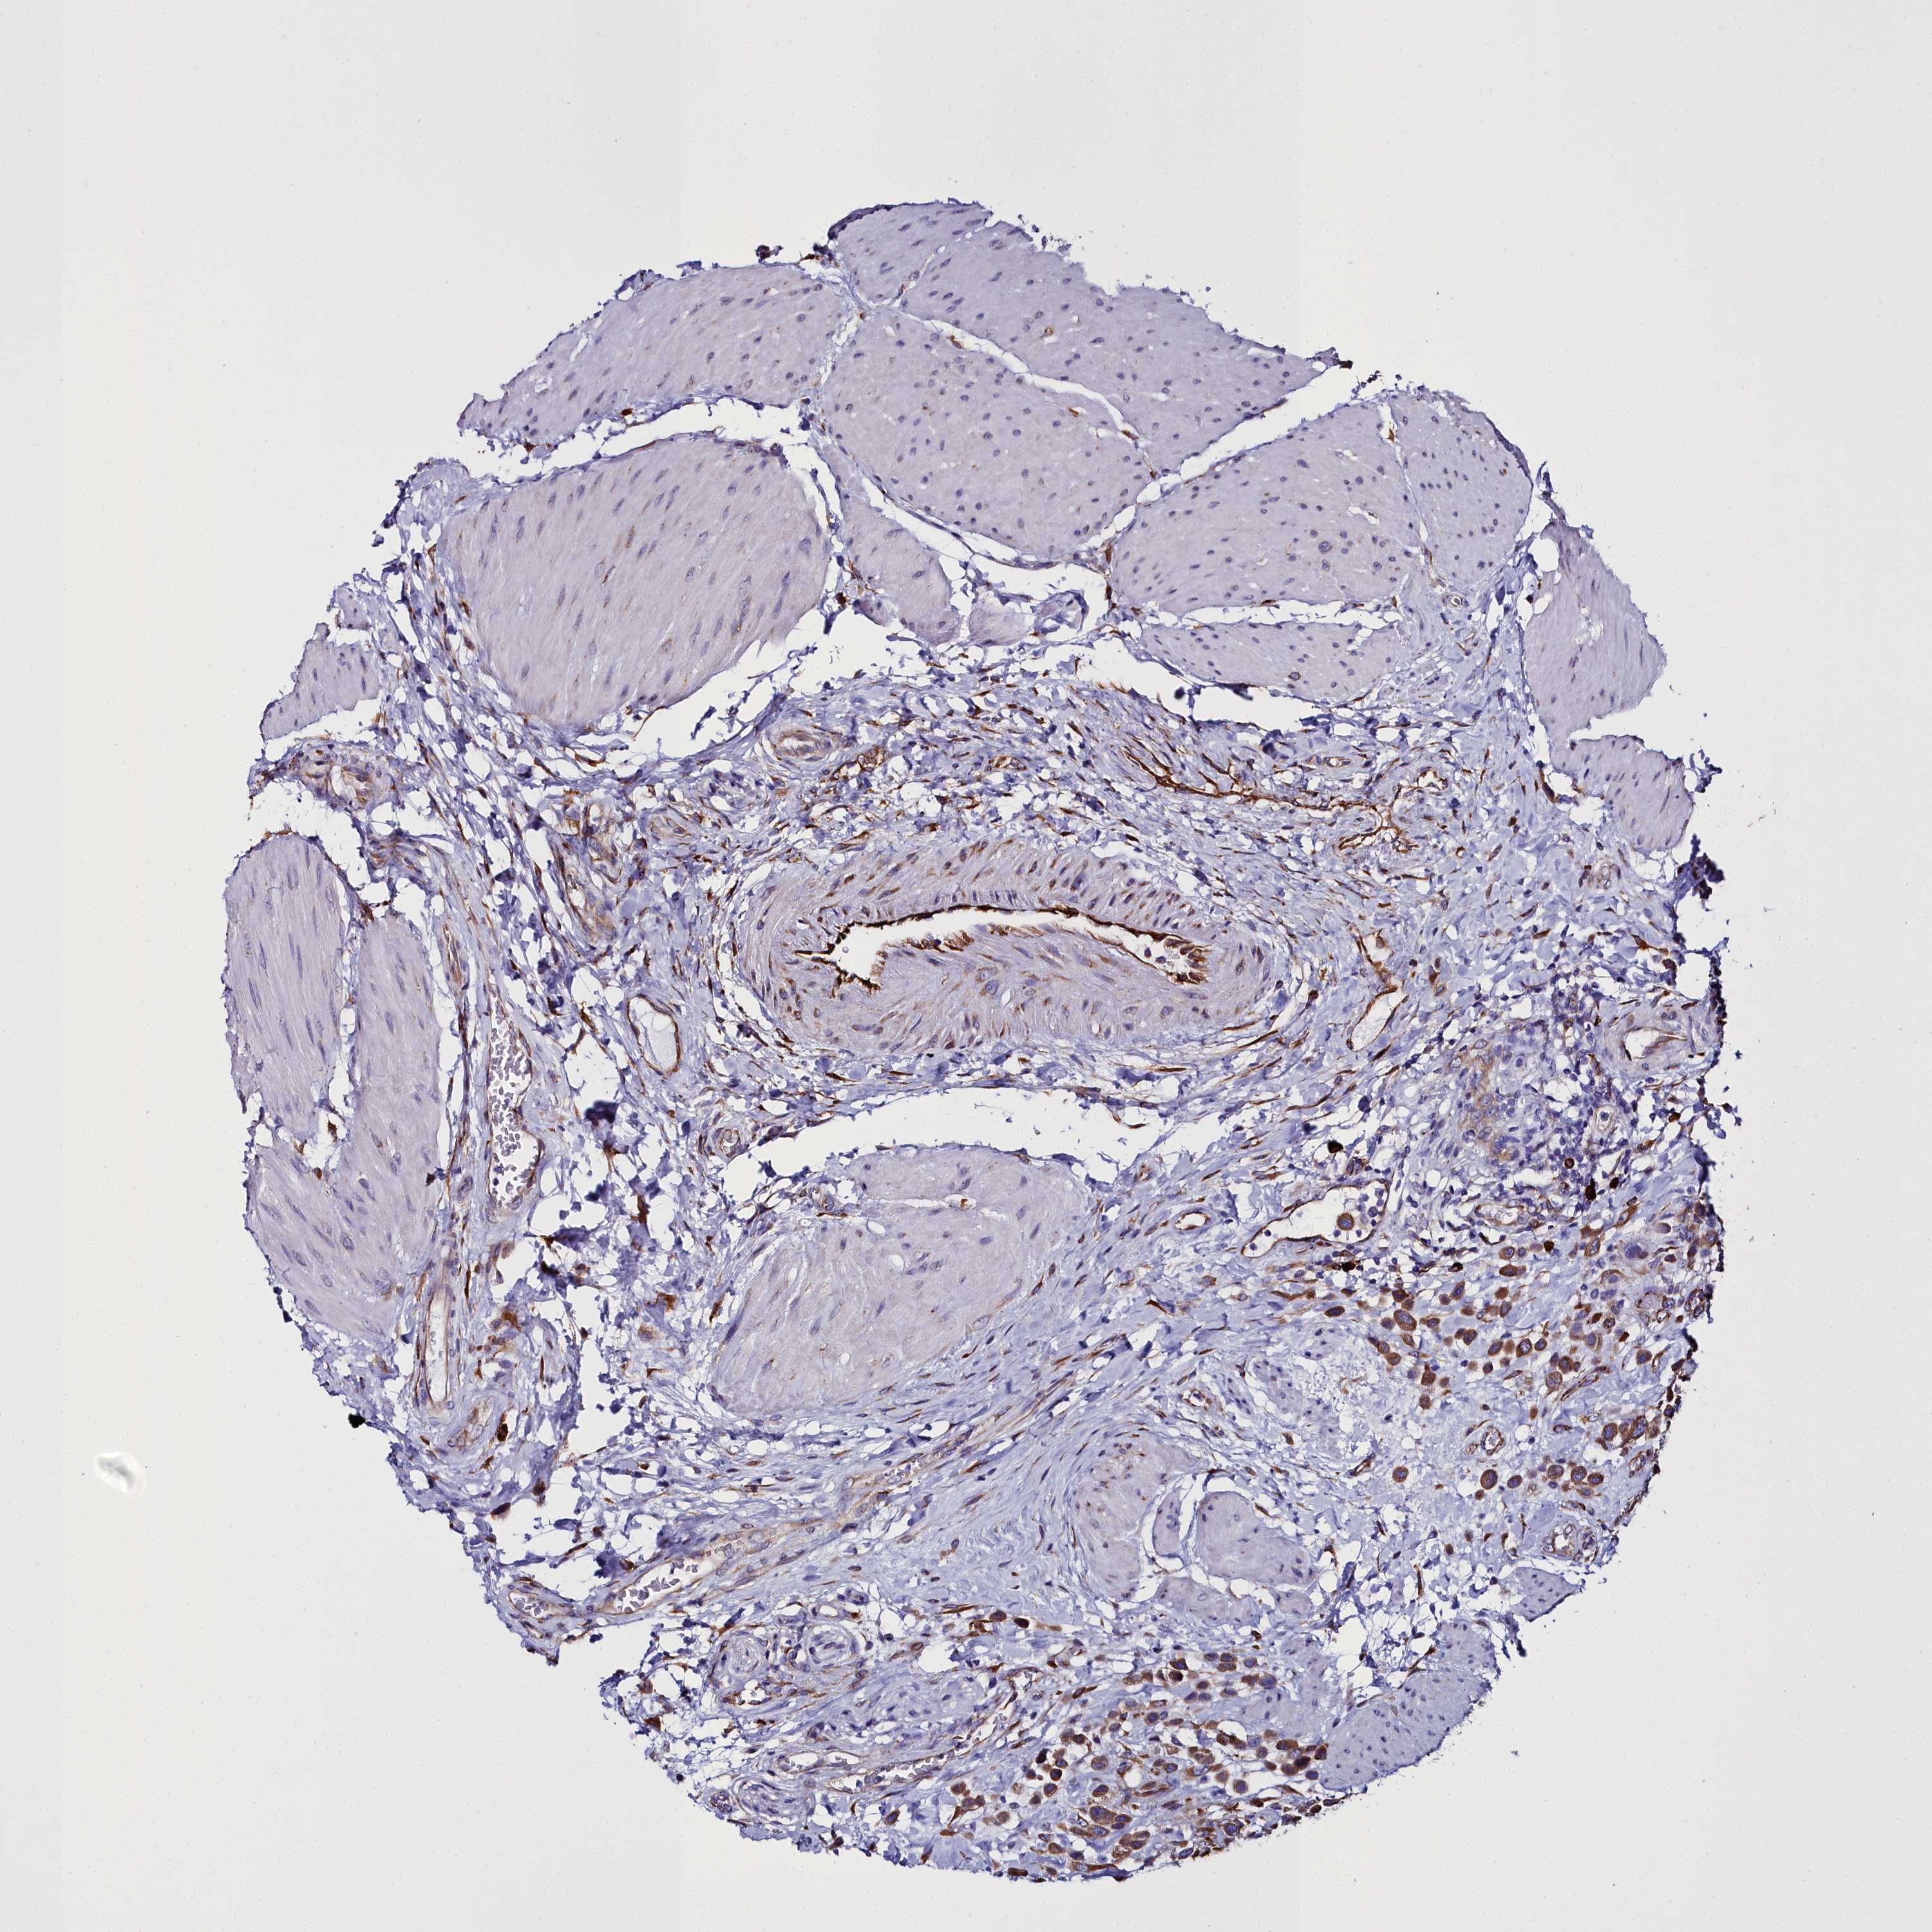

UROTHELIAL CANCER - Protein expressioni

A mouse-over function shows sample information and annotation data. Click on an image to view it in a full screen mode. Samples can be filtered based on level of antibody staining by selecting one or several of the following categories: high, medium, low and not detected. The assay and annotation is described here.

Note that samples used for immunohistochemistry by the Human Protein Atlas do not correspond to samples in the TCGA dataset.

Antibody stainingi

Antibody staining in the annotated cell types in the current human tissue is reported as not detected, low, medium, or high, based on conventional immunohistochemistry profiling in selected tissues. This score is based on the combination of the staining intensity and fraction of stained cells.

Each image is clickable and will lead to virtual microscopy that enables deeper exploration of all samples and also displays staining intensity scores, fraction scores and subcellular localization as well as patient and tissue information for each sample.

Antibody HPA034677

Antibody HPA034678

Staining

High

Medium

Low

Not detected

Intensity

Strong

Moderate

Weak

Negative

Quantity

>75%

75%-25%

<25%

None

Location

Nuclear

Cytoplasmic/membranous

Cytoplasmic/membranous,nuclear

Urothelial carcinoma, Low grade